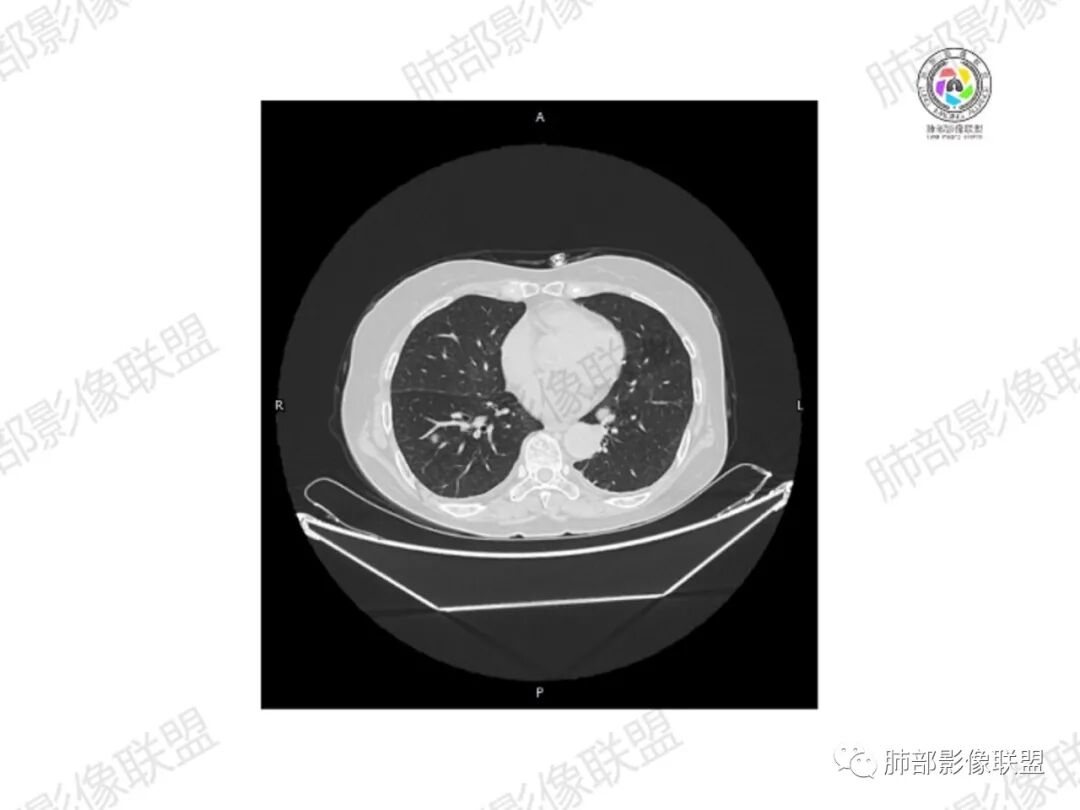

5.双肺多发类圆形结节影,边界清楚,随机分布,其间多见钙化密度影。

6.双肺门及纵隔未见肿大淋巴结。

3.双肺病灶符合转移瘤,伴有中央部分钙化者也以骨肉瘤转移较为多见。